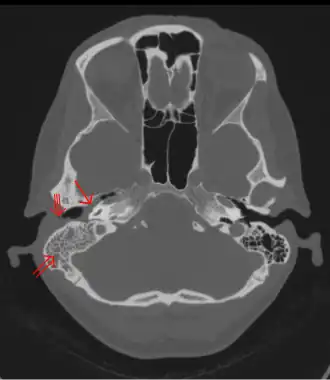

Photographie d'une mastoïdite, inflammation de la mastoïde.

Une mastoïdite est une inflammation de la mastoïde. Il s'agit d'une forme de complication de l'otite, pouvant survenir en raison de la communication entre les cavités de l'oreille moyenne et celles de la mastoïde.